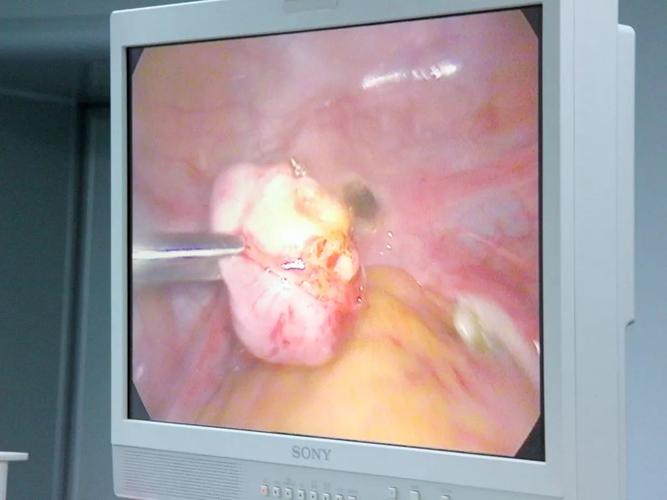

(图) 宫颈锥形切除术

宫颈囊肿微创手术图

宫颈囊肿怎么手术图片

宫颈囊肿刺破图